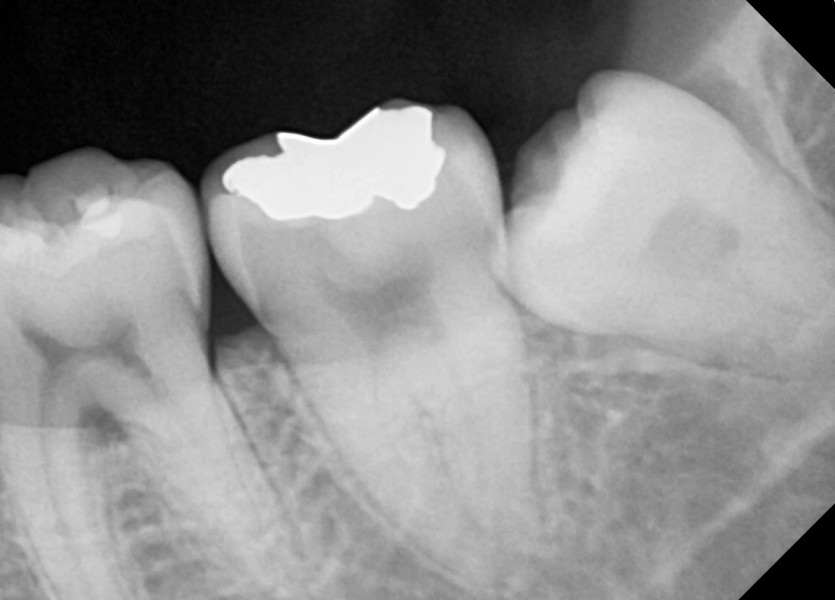

#38 사랑니 발치

구강 외과 전문의가 당일 발치했습니다.